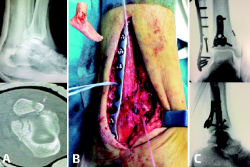

Las ventajas de la reparación anatómica son indudables, dado que proporciona reducciones mucho más precisas y estables, de forma que se puede obviar la necesidad de dispositivos transindesmales ahorrando costes y la necesidad de reintervenciones para la retirada de los mismos(27,28); sin embargo, también se encuentran una serie de desventajas, como el aumento del tiempo quirúrgico por la mayor agresividad de los abordajes o la necesidad de cambiar de posición al paciente durante la cirugía. Para minimizar esta posibilidad, nosotros utilizamos el abordaje posterolateral en decúbito prono cuando no se prevé necesario reparar fragmentos dependientes del LTFAI y el abordaje lateral clásico asociado a una modificación del posteromedial en decúbito supino prolongando la incisión para el maléolo interno por la cresta tibial medial y accediendo al aspecto posterior de la tibia por delante del tendón tibial posterior y el paquete neurovascular, lo cual permite tener acceso tanto a las estructuras anteriores por el abordaje lateral como a las posteriores por el medial y da incluso la posibilidad de observar la reducción articular a través del foco de fractura del maléolo interno (Figuras 3 y 4).

Figura 3. Casos clínicos con abordaje posterolateral (arriba), señalando con la pinza mosquito el ligamento tibiofibular posteroinferior, y con abordaje posteromedial (abajo), donde se observa la reducción del maléolo posterior y toda la articulación a través del foco de fractura del maléolo medial separado por los ganchos.

Figura 4. Caso tratado con el enfoque anatómico. En la tomografía computarizada preoperatoria se observa avulsión del ligamento tibiofibular anteroinferior y fractura maleolar posterior (A). En supino, abordaje lateral clásico con acceso a la articulación tibiofibular distal, comprobando la reducción y reanclando el ligamento con arpón (B). Después, abordaje posteromedial en supino para acceso medial y posterior. C: resultado final.